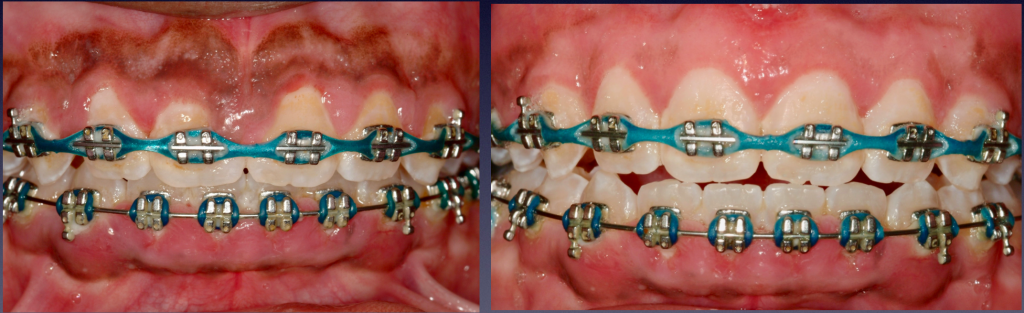

Gummy Smile Correction, with Braces